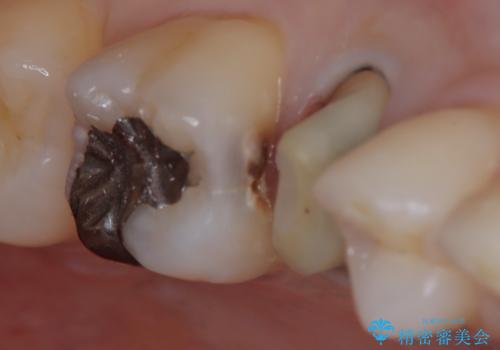

【セラミックインレー】定期検診にて虫歯を発見

- 定期検診にて虫歯を発見したため、セラミッククラウン、セラミックインレーにて治療を行いました。

小臼歯の虫歯は歯髄に近かったため、部分的断髄法にて歯髄を部分的に保存した治療をおこなっています。